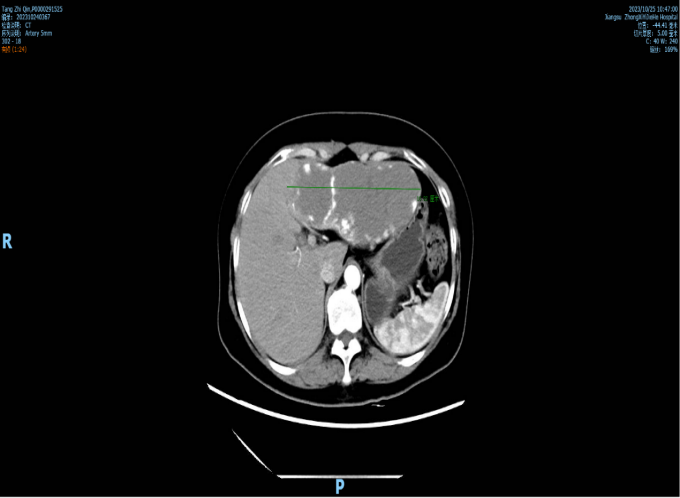

一吃饭腹部就胀痛,CT检查见16厘米肿瘤赫然在目

经CT检查,结果显示刘女士肝脏左外叶处,一个直径达到16厘米的巨大肿瘤赫然在目,最终确诊为血管瘤。肝血管瘤是一种肝脏内大量的动静脉血管畸形构成的团状结构,是最常见的肝脏良性肿瘤,往往是在体检中被人意外发现。

当肝血管瘤较小、未引起身体不适时,暂时不需要手术治疗,只需定期到医院复查肝脏B超即可。但是刘女士肝脏上的瘤体太大,压迫到周围脏器,所以才出现了进食后上腹胀痛的症状。

周主任表示,患者的血管瘤已经完全占据了肝脏左外叶,如果不立刻进行瘤体切除手术,肿瘤只会越长越大,压迫脏器的症状会更加明显。一旦瘤体破裂出现大出血,后果将不堪设想。同患者说明情况后,周主任将其收住入院。